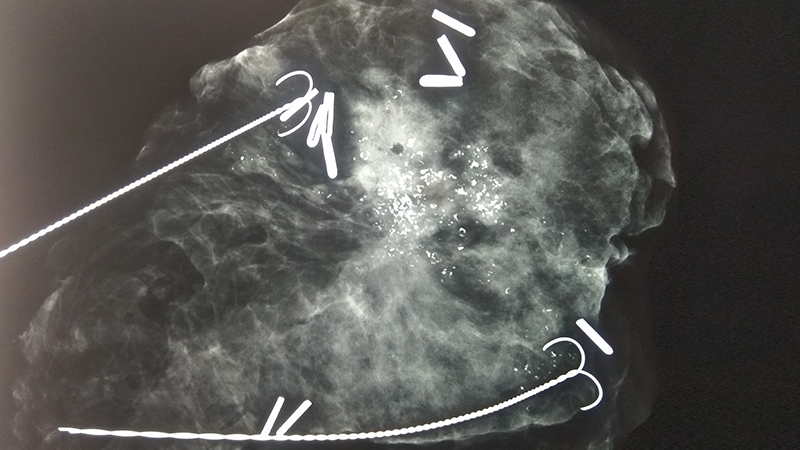

Αφαίρεση αψηλάφητων βλαβών μαστού με συρμάτινο οδηγό

Αφαίρεση αποτιτανώσεων (ασβεστώσεων) μαστού